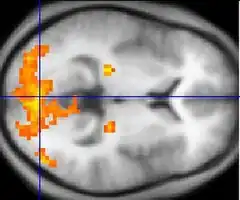

Colour vision area shown as V8 on upper image

Anatomical and physiological studies have established that the colour centre begins in V1 and sends signals to extrastriate areas V2 and V4 for further processing. V4 in particular is an area of interest because of the strength of the colour receptive fields in its neurons.[4] V4 was initially identified in macaque monkey visual cortex experiments. Originally, it was proposed that colour was selectively processed in V4. However, this hypothesis was later rejected in favour of another hypothesis which suggested that V4 and other areas around V4 work together to process colour in the form of multiple colour selective regions.[5] After identification of V4 as the colour-selective region in macaque monkeys, scientists began searching for a homologous structure in the human cortex. Using fMRI brain imaging, scientists found three main areas stimulated by colour: V1, an area in the ventral occipital lobe, specifically the lingual gyrus, which was designated as human V4, or hV4, and another area located anteriorly in the fusiform gyrus, designated as V4α.[4][6]